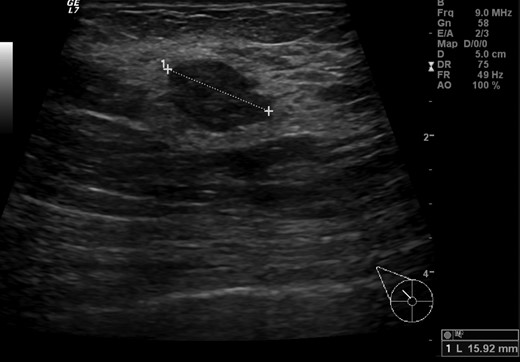

Diagnostic mammogram revealed a 15 mm lump in between the right breast upper quadrants—BIRADS 3. Core needle biopsy was performed, showing a hyalinized fibroadenoma. Thorax, abdomen and pelvis CT scans as well as bone scintigraphy did not reveal metastatic disease. Multidisciplinary team decision was to maintain close surveillance and repeat radiological evaluation in three months. Re-evaluation mammogram and ultrasonography revealed a highly suspicious mass in the upper outer quadrant of the right breast (Fig. 2). No further breast or axillary suspicious radiological abnormalities were detected. Core needle biopsy showed a lobular invasive carcinoma, positive for (CK7) and negative for E-cadherin. No vascular or lymphatic invasion were present. The 100% of cells were positive for estrogen and progesterone receptors, negative for HER2 and Ki67 was 20%. PET/CT scan showed no abnormal hyper metabolic lesions.

Breast ultrasonography showing an irregular 15 mm hypoechoic lump with no acoustic shadowing between right upper quadrants.